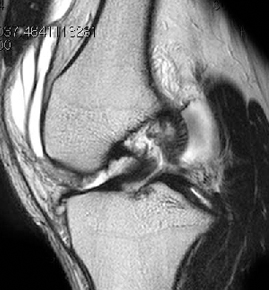

• ACL 손상 방사선 사진3